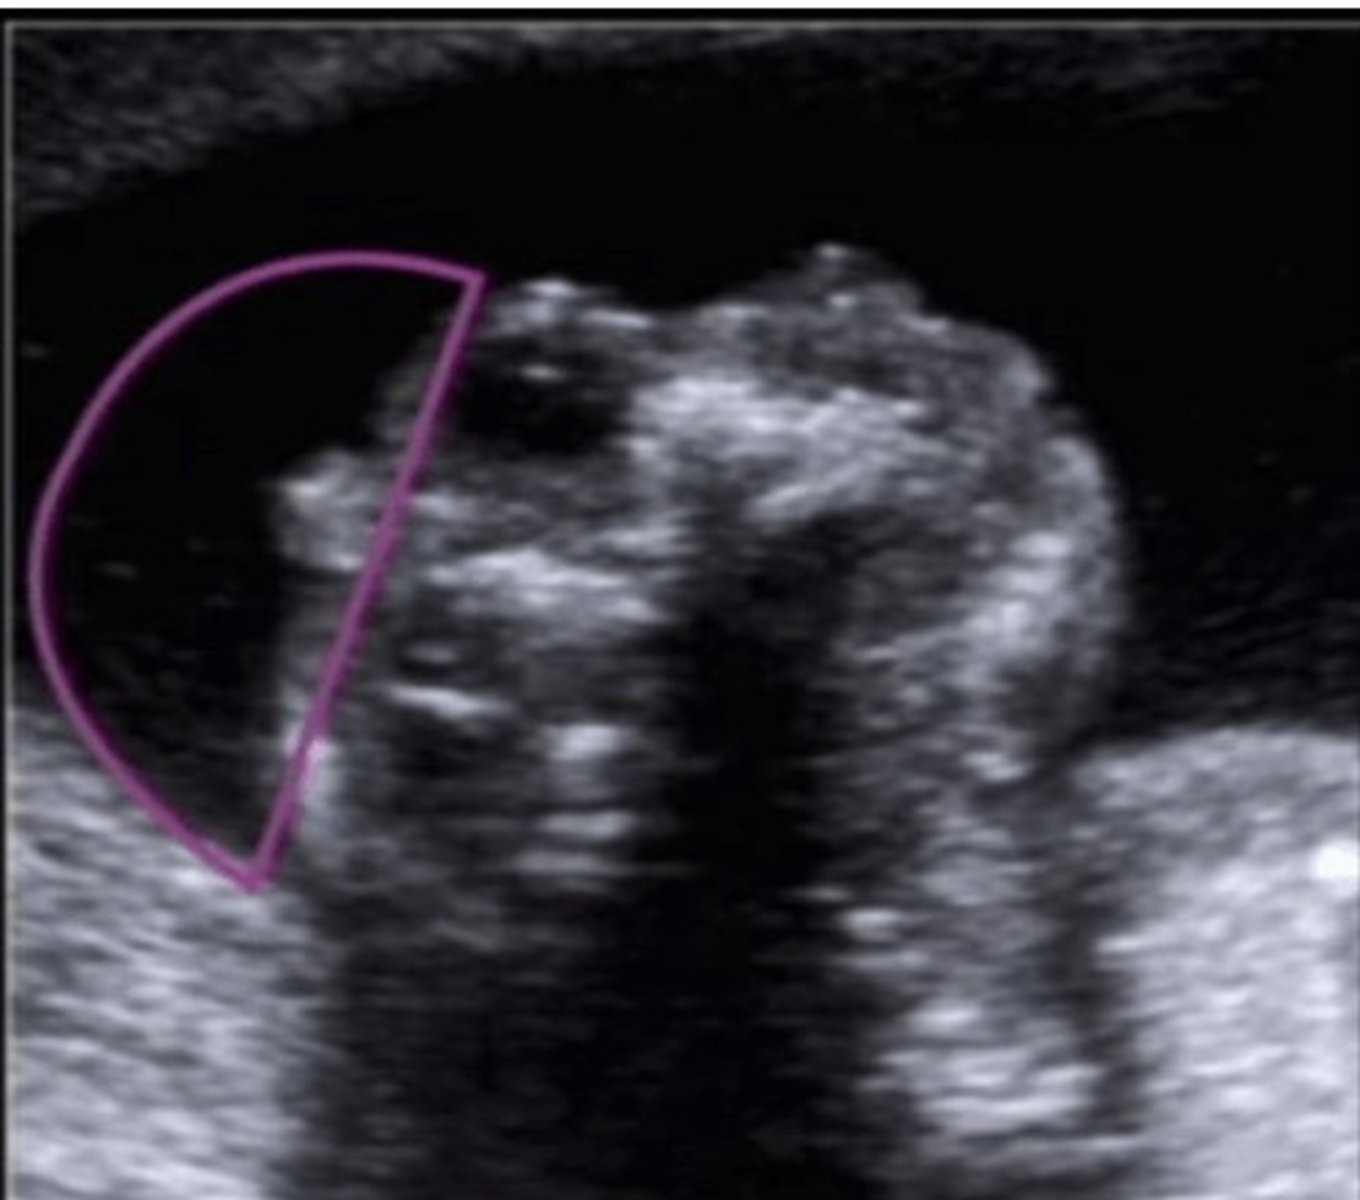

Type 2 Thanatophoric Dysplasia

Short straight femurs

Clover skull